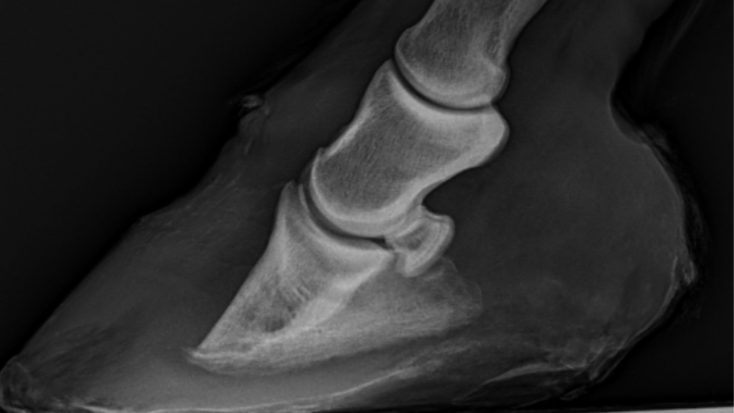

De hals van het paard vormt vaak een diagnostische uitdaging. In dit webinar bespreekt Dr. Katrien Vanderperren, Europees specialist in veterinaire beeldvorming, stap voor stap hoe je radiografie van de hals optimaal uitvoert en interpreteert.

Aan de hand van talrijke praktijkvoorbeelden komt zowel de techniek van opname (positie, belichting, valkuilen) als de beoordeling van de beelden uitgebreid aan bod. Daarnaast wordt ingegaan op de belangrijkste radiografische afwijkingen van de halswervels en hun klinische relevantie bij aandoeningen zoals ataxie, nekpijn en artropathie.